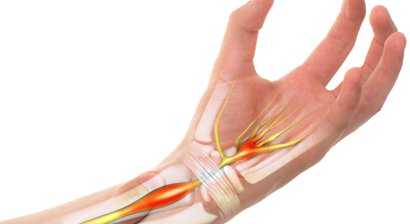

Handchirurgie

Als Facharzt für Orthopädie und orthopädische Chirurgie setze ich bei meinen Patienten primär auf konservative Therapien - getreu der Philosophie "Schmerzfrei ohne Spritzen" setze ich alles daran, um meinen Patienten im Rahmen einer individuellen und bedürfnisorientierten Th...